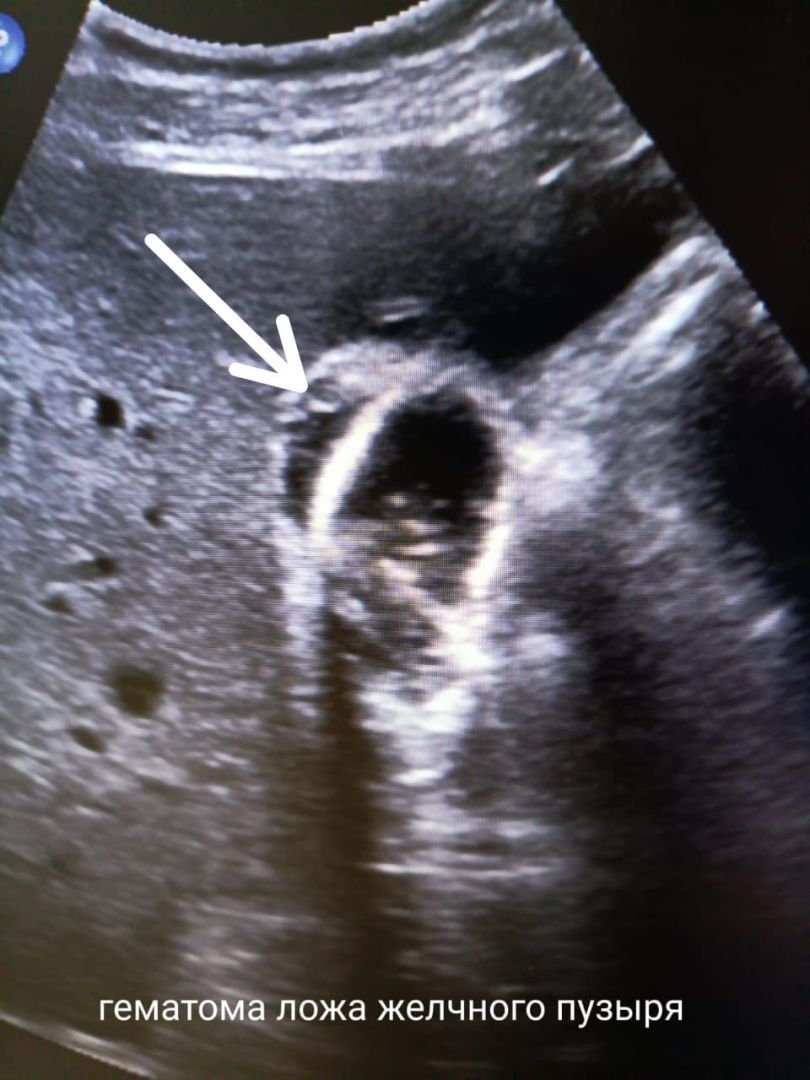

• Ставропольские медики спасли пациента с отрывом желчного пузыря без операции

Врачи городской клинической больницы скорой медицинской помощи провели успешное нехирургическое лечение частичного отрыва желчного пузыря, применив консервативную терапию вместо экстренной операции. О случае рассказали в краевом министерстве здравоохранения.

Частичный отрыв желчного пузыря — опасное состояние, которое обычно требует экстренного хирургического вмешательства. В данной ситуации на месте травмы образовалась гематома.

Специалисты выбрали тактику консервативного ведения пациента. Она включала динамическое ультразвуковое наблюдение, контроль результатов анализов, применение гемостатических и антибактериальных препаратов.

Гематома стабилизировалась и со временем полностью рассосалась без хирургического вмешательства. Главный результат — желчный пузырь удалось сохранить.